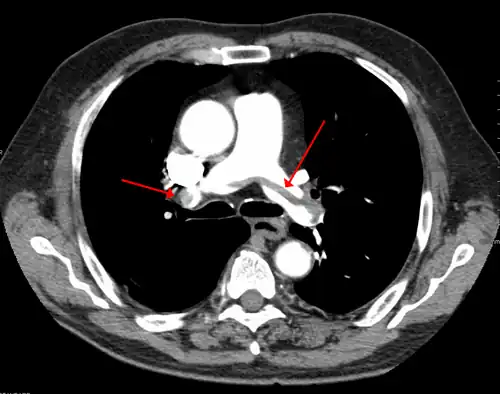

A pulmonary embolism (PE) occurs when a blood clot from a deep vein (a DVT) detaches from a vein (embolizes), travels through the right side of the heart, and becomes lodged as an embolus in a pulmonary artery that supplies deoxygenated blood to the lungs for oxygenation.[28] Up to one-fourth of PE cases are thought to result in sudden death.[12] When not fatal, PE can cause symptoms such as sudden onset shortness of breath or chest pain, coughing up blood (hemoptysis), and fainting (syncope).[29][30] The chest pain can be pleuritic (worsened by deep breaths)[29] and can vary based upon where the embolus is lodged in the lungs. An estimated 30–50% of those with PE have detectable DVT by compression ultrasound.[30]